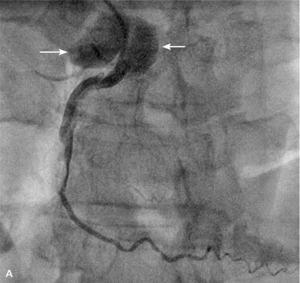

RYCINA 1. Rozwarstwienie pnia lewej tętnicy wieńcowej (strzałki) końcówką głęboko wprowadzonego cewnika.

Najczęstszym powikłaniem sercowym jest nagłe zamknięcie naczynia w czasie zabiegu lub wkrótce po nim. Dochodzi do niego zazwyczaj wskutek rozwarstwienia ściany poszerzanej tętnicy, zakrzepicy w stencie lub wystąpienia tzw. zjawiska no flow. W czasach przed upowszechnieniem się stentów dyssekcja zamykająca naczynie często prowadziła do pilnej operacji kardiochirurgicznej. Obecnie powikłanie to rzadko prowadzi do trwałej okluzji tętnicy wieńcowej z wyjątkiem tzw. dyssekcji spiralnej obejmującej bardzo długi odcinek, czasami nawet całe naczynie. Zazwyczaj implantacja jednego lub więcej stentów rozwiązuje problem. Dyssekcja może być trudna do zaopatrzenia, jeśli dojdzie do niej przed wprowadzeniem prowadnika lub gdy wprowadzenie stentu jest niemożliwe ze względu na krętość naczynia lub obecność zwapnień. Szczególnym rodzajem dyssekcji jest rozwarstwienie początkowego odcinka naczynia cewnikiem prowadzącym. Takie zdarzenie jest szczególnie niebezpieczne, jeśli dotyczy pnia lewej tętnicy wieńcowej (ryc. 1) i może się skończyć nagłym zgonem pacjenta. Czasami krew wnikająca do ściany naczynia blisko miejsca odejścia rozwarstwia opuszkę aorty. Taka dyssekcja może szybko objąć nawet całą aortę aż do jej podziału (ryc. 2A, B), co często wymaga pilnej interwencji chirurgicznej.